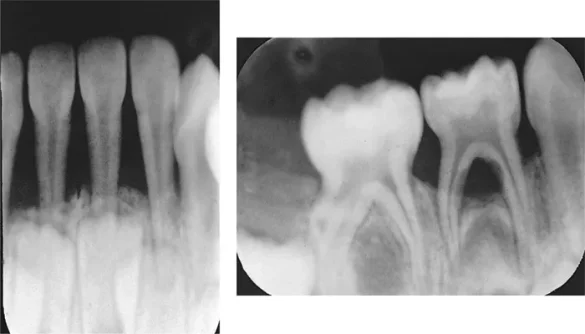

In the advanced stages of periodontal disease, bone loss becomes a significant concern. The supporting bone deteriorates, which can lead to tooth mobility, and in some cases, tooth loss. Understanding whether this bone can regenerate is crucial for both patients and dental professionals.

The ability of bone to regenerate after periodontal disease depends on several factors, including the severity of the bone loss, the type of treatment employed, and the overall health of the patient. While bone loss due to periodontal disease is often considered irreversible, modern dental techniques have made it possible to encourage bone regeneration under certain circumstances.